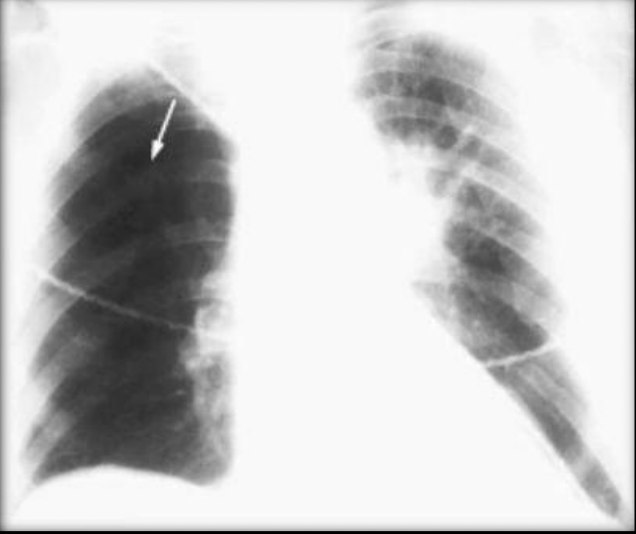

Signo de Western Mark:

Hiperlucencia periférica por oligoemia

Dilatación de la arteria pulmonar